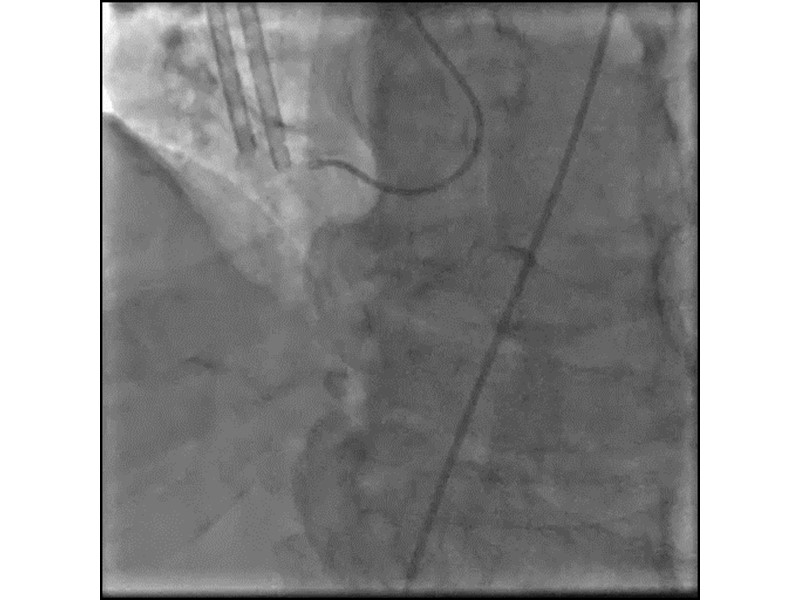

Distal left main stenosis: how to treat optimally with dedicated bifurcation stent BiOSS Lim C. Case-based session

- To learn about multiple technological options with dedicated bifurcation stent for complex left main bifurcation lesions

- To learn about applicability of the dedicated bifurcation stent for the different clinical presentations